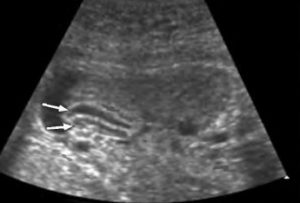

Патология может быть классифицирована как полное отсутствие органа или его удвоение, за исключением случаев хирургического удаления. Агнезия является редким явлением и часто несовместима с жизнью. В некоторых случаях пузырь может быть обнаружен в диафрагмальной грыже. Удвоение может быть полным, когда существуют два отдельных органа с разными шейками и каналами, или неполным, когда происходит разделение продольной перегородкой, но протоки и шейка остаются общими.

Ультразвуковое исследование (УЗИ) является наиболее точным методом диагностики патологических изменений в структуре и форме пищеварительного органа. Оно позволяет получить информацию о состоянии, структурных особенностях и функциональности стенок и протоков. УЗИ может быть общим или проводиться с нагрузкой, когда данные снимаются после употребления желчегонного завтрака пациентами. В случае нечеткой визуализации системы с протоками на УЗИ, пациентам назначают компьютерную томографию (КТ) и магнитно-резонансную томографию (МРТ).